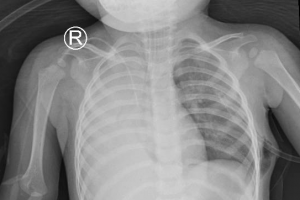

Cứu sống một trường hợp trẻ dị dạng bẩm sinh phế quản gốc bên phải xuất phát bất thường từ thực quản

Vừa qua Bệnh viện Nhi Đồng Thành Phố tiếp nhận trẻ Ng. Kh. H. 3 tháng tuổi, nữ, ngụ ở Bình Chánh, TP. Hồ Chí Minh. Khai thác bệnh sử trẻ bệnh 1 tuần, khởi phát...